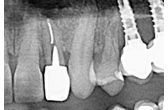

di chirurgia orale e implantologia